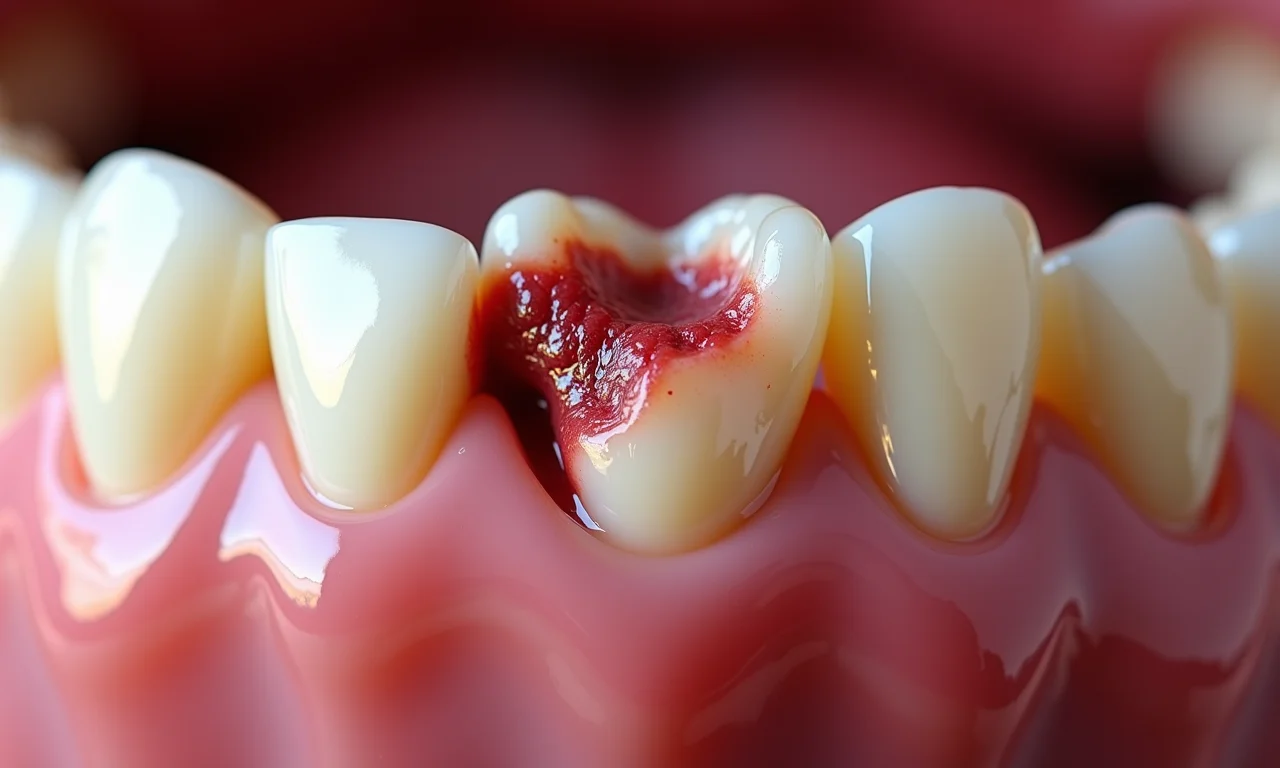

Siso Incluso ou Semi-Incluso

Às vezes, o siso não consegue nascer completamente e fica preso no osso (incluso) ou nasce parcialmente (semi-incluso). Nesses casos, ele pode causar inflamação na gengiva (pericoronarite), dor, inchaço e até infecção. Fica tranquila, tem solução!